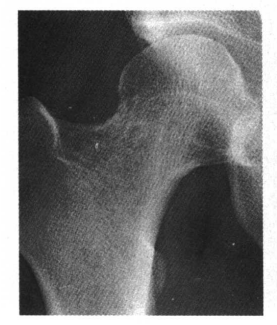

3.股骨颈环状透亮区,周边可见极薄硬化缘,为一常见现象,一般认为滑膜疝入皮质形成的皮质小坑,无临床意义(图3)。

图3 股骨颈环状透亮区,为滑膜疝入皮质形成的皮质下小坑,无临床意义